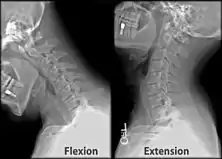

Behind either condyle of the lateral parts of occipital bone is a depression, the condyloid fossa (or condylar fossa), which receives the posterior margin of the superior facet of the atlas when the head is bent backward; the floor of this fossa is sometimes perforated by the condyloid canal, through which an emissary vein passes from the transverse sinus.